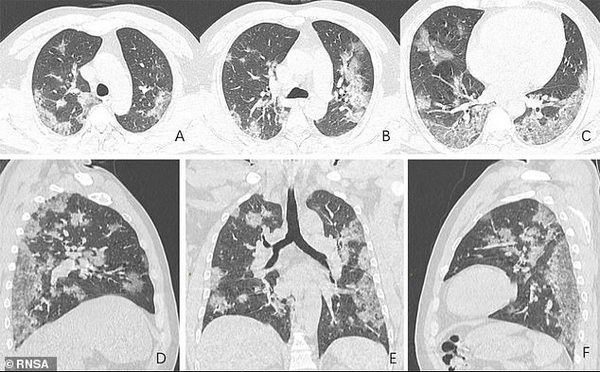

В частности, Радиологическое общество Северной Америки (Radiological Society of North America) опубликовало снимки легких 44-летнего жителя Китая, работавшего на рынке в Ухане (откуда, как полагают, начала распространяться эпидемия) и умершего от COVID-19.

На фото видны все увеличивающиеся со временем белые пятна в нижней части дыхательных органов. Радиологи называют это симптомом «матового стекла». Он отражает различные патологические изменения в легочной ткани.

Как подчеркивает издание Daily Mail, на фото заметно как присутствие жидкости в легких мужчины постепенно становится все более выраженным — от первого изображения A до последнего F.

Китаец поступил в больницу в декабре 2019 года — после того, как у него в течение двух недель наблюдался сильный кашель и высокая температура. Врачи диагностировали пневмонию и острый респираторный дистресс-синдром. Несмотря на усилия медиков, пациент скончался неделю спустя.